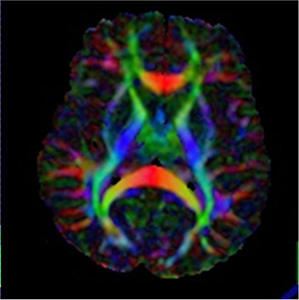

Diffusion tensor imaging (DTI) is a measure of water diffusion in brain tissue and will provide information of white matter structure in the brain on a voxel-by-voxel basis. DTI scans derive neural tract directional information using multidimensional vector algorithms typically based on three or more gradient directions, which is the minimum information in order to compute the diffusion tensor. From the diffusion tensor, diffusion anisotropy measures such as the fractional anisotropy (FA) can then be computed.

The result is visualized as color-coded neuronal tracts where the x-, y- and z- directions typically are coded in red, green and blue, respectively (picture to the right). Recent advances in DTI measurements also allow the researcher to visualize the pathway of a bundle through brain tissue, called DTI tractography. DTI has revealed structural abnormalities related to white matter tracts in a range of psychiatric and neurological disorders and is increasingly used in clinical practice.